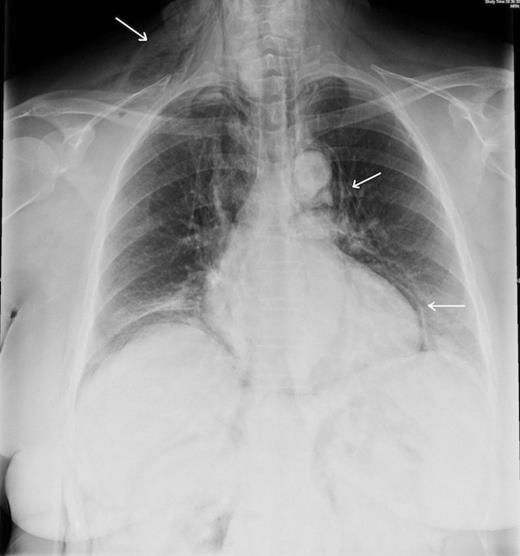

Full blood count was normal and a chest radiograph on admission showed subcutaneous emphysema, pneumo-mediastinum and pneumopericardium but no other abnormality (fig. 1). Computerised Tomography of the abdomen showed in addition, pneumoperitoneum and pneumoretroperitoneum (fig. 2). A water-soluble contrast examination of the colon failed to reveal evidence of a colonic perforation.

CXR showing subcutaneous emphysema, pneumomediastinum and pneumopericardium